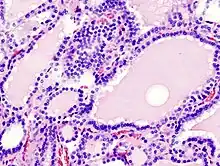

.jpg)